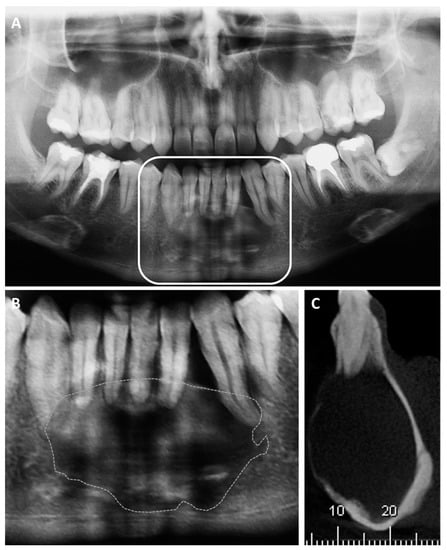

The extraoral examination did not show enlargement of the facial contour, and the intraoral examination showed vestibular swelling between the mandibular canines, in addition to a slight bulge in the lingual region, with healthy mucosa and no signs of inflammation. Panoramic radiography revealed a well-defined unilocular radiolucent lesion involving the mandibular incisors and canines bilaterally, reaching the mandibular base (Figure 1). In addition, the root of the left inferior canine appeared to be slightly displaced, suggesting a lesion with a high growth rate. Diagnostic hypotheses included central giant cell granuloma and ameloblastoma, substantiating the need for an incisional biopsy, which was performed under local anesthesia, after signature of the informed consent by the patient. Moreover, the patient was referred for a CT scan for a precise diagnosis, determining its borders and anatomical relation with vascular and nervous structures, in order to establish an appropriate surgical plan.

Figure 1. (A,B)—Initial panoramic radiography, revealing a well-defined unilocular radiolucent lesion between inferior canines, reaching the mandibular base. The dashed line highlights the limits of the lesion. (C)—Representative sagittal cut of the preoperative CT scan, confirming a significant radiolucent lesion involving the vestibular and lingual regions.